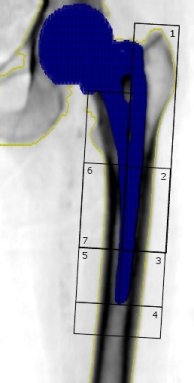

Wokół endoprotezy kości udowej |

Wysoce specjalistyczna procedura, przeznaczona dla pacjentów po endoprotezoplastyce stawów biodrowych, umożliwiająca analizę gęstości mineralnej kości (ang. bone mineral density - BMD) wokół trzpienia jakiejkolwiek endoprotezy.

Badanie jest przydatne do monitorowania zmian gęstości kości w strefach Gruena, co umożliwia oszacowanie ryzyka obluzowania endoprotezy w przyszłości. Oznaczenie powinno być wykonane bezpośrednio po zabiegu ortopedycznym, a następnie w pierwszym roku po operacji przynajmniej dwukrotnie. |